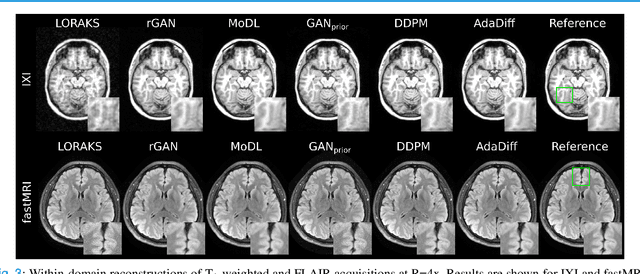

Abstract:Deep MRI reconstruction is commonly performed with conditional models that map undersampled data as input onto fully-sampled data as output. Conditional models perform de-aliasing under knowledge of the accelerated imaging operator, so they poorly generalize under domain shifts in the operator. Unconditional models are a powerful alternative that instead learn generative image priors to improve reliability against domain shifts. Recent diffusion models are particularly promising given their high representational diversity and sample quality. Nevertheless, projections through a static image prior can lead to suboptimal performance. Here we propose a novel MRI reconstruction, AdaDiff, based on an adaptive diffusion prior. To enable efficient image sampling, an adversarial mapper is introduced that enables use of large diffusion steps. A two-phase reconstruction is performed with the trained prior: a rapid-diffusion phase that produces an initial reconstruction, and an adaptation phase where the diffusion prior is updated to minimize reconstruction loss on acquired k-space data. Demonstrations on multi-contrast brain MRI clearly indicate that AdaDiff achieves superior performance to competing models in cross-domain tasks, and superior or on par performance in within-domain tasks.